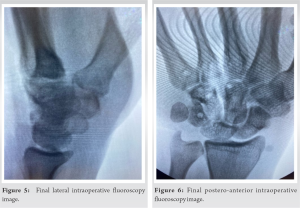

Figs. 5 and 6 show the final intraoperative fluoroscopy images after removal of the provisional fixation. The patient was placed in a post-operative splint and was kept with the wrist immobilized and fingers free for 6 weeks, followed by aggressive hand therapy to treat any subsequent stiffness and weakness. The rehabilitation protocol followed in this case consisted of 6 weeks of immobilization followed by 3 weeks of range of motion stretching. This was followed by light strengthening with progression to full release of all activities at 3 months post-operatively.